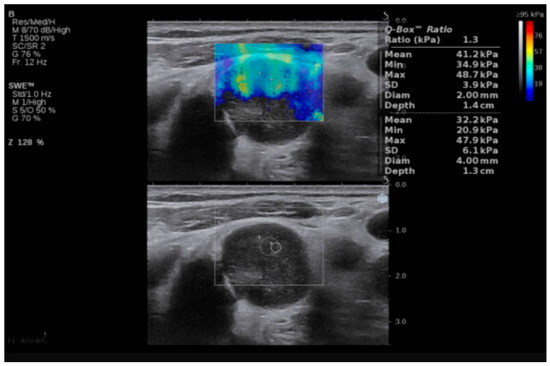

Examples of SWE analyses of malignant lymph nodes are provided in Figure 1 and Figure 2, and descriptive statistics of SWE by histopathology type (participants with benign cervical lymph nodes, participants with lymphoma and cervical lymphadenopathy, and participants with cervical lymph node metastasis of solid tumors) are shown in Table 3. The maximum SWE value for patients with benign pathologies was 35 kPa, which is lower than both minimal values for lymphoma (40 kPa) and metastases (50 kPa). These results suggest that SWE values under 40 kPa are associated with benign cervical lymph nodes. Given the differences between the benign and malignant lymph nodes highlighted by the SWV, we further concentrated our attention on the differences in tissue stiffness that can be seen in the malignant group and the capacity of SWE in differentiating between the metastatic and lymphoma lymph nodes.

Figure 2.

SWE of an LN in a 64-year-old patient with LN metastasis from a squamous cell carcinoma of the anterior floor of the mouth. LN, lymph node; SWE, shear wave elastography.